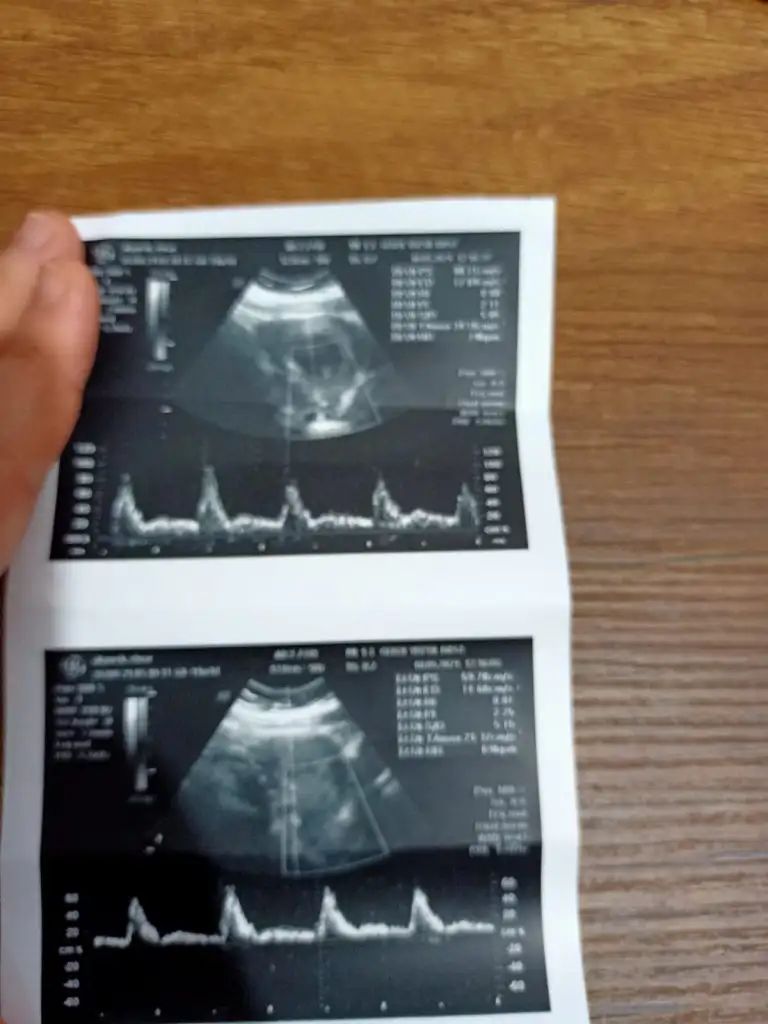

Merhaba nolur benim için de yorumda bulunun mümkün ise🙏🏻 Ikra meyra Ikra meyra şimdiden çok tşk ederim🌻

Eklentiler

• 0ECD12B2-B3A6-4EF7-B739-134B8AC8C35E.webp

0ECD12B2-B3A6-4EF7-B739-134B8AC8C35E.webp

36 KB · Görüntüleme: 76

• 19B0E091-AC23-4949-AA62-7A96B81FB2FA.webp

19B0E091-AC23-4949-AA62-7A96B81FB2FA.webp

30 KB · Görüntüleme: 76